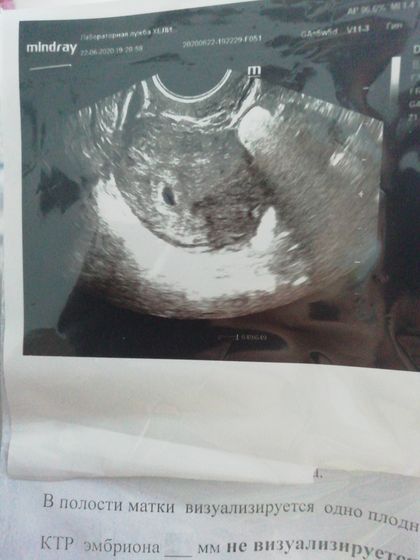

Девочки, привет, сегодня 22 день после овуляции, сделала сегодня узи, итог таков: плодное яйцо 4 мм, соответствует сроку беременности 3-4 неоели, но не видят желтого мешочка, хотя она сказала, что немного просматривается, но пока плохо, так как срок маленький. Овуляция была поздняя, на 20 день цикла, по месячным срок ставят 5 недель 5 дней. Врач сказала, что по акушерскому сроку не соответствует размер плодного яйца, а по эмбриональному соответстветсвует. Вот и что думать теперь, все ли хорошо?